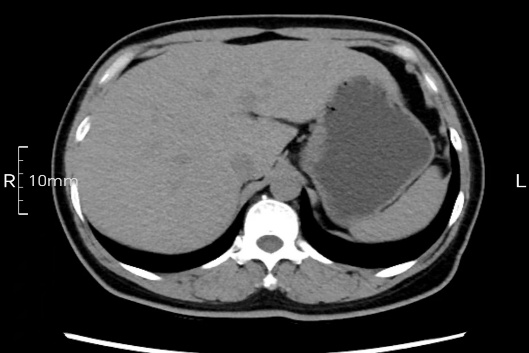

完美禁食且喝飽飽,胃壁完美展現(xiàn)。